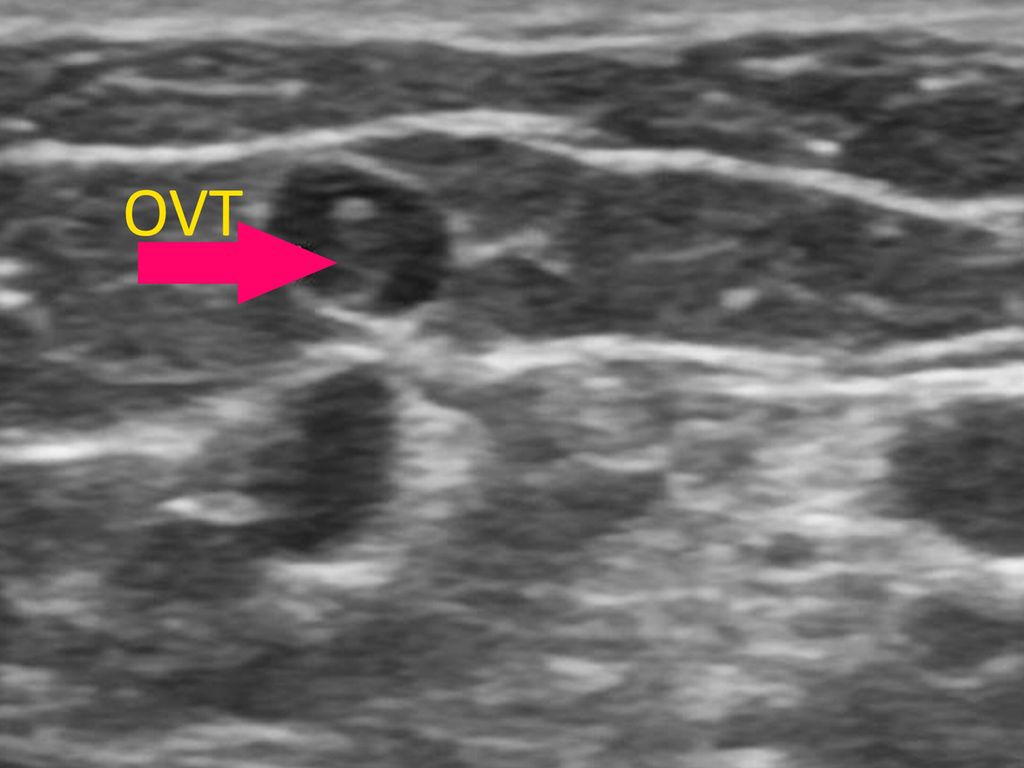

Die oberflächliche Venenthrombose (OVT) und Antikoagulation bei OVT